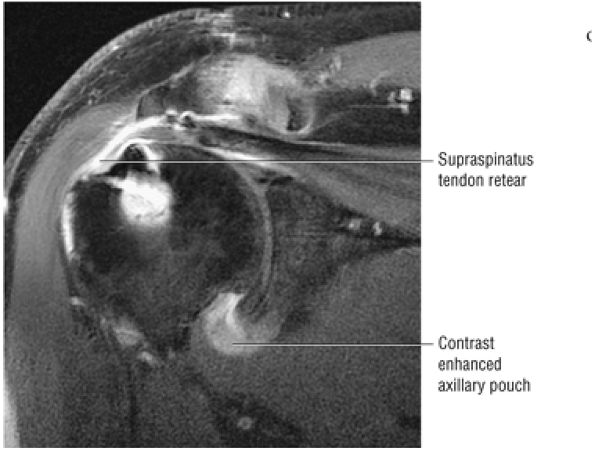

Improved detection of rotator cuff tears, including partial tears

in addition to GRE T2*-weighted images. Contrast enhancement with intra-articular gadolinium diethylenetriamine pentaacetic acid (Gd-DTPA) may increase diagnostic conspicuity in partial articular surface tears of the rotator cuff, helps distinguish severe tendinitis from rotator cuff tears, and improves visualization of the capsulolabral anatomy of the glenohumeral joint.16,26,29,31 T1-weighted Gd-DTPA images also minimize the effect of magnetic susceptibility seen with GRE images in the postoperative cuff. With or without gadolinium enhancement, MR arthrography is not required for routine studies when there is access to phased-array shoulder coils and appropriate imaging sequences are used.